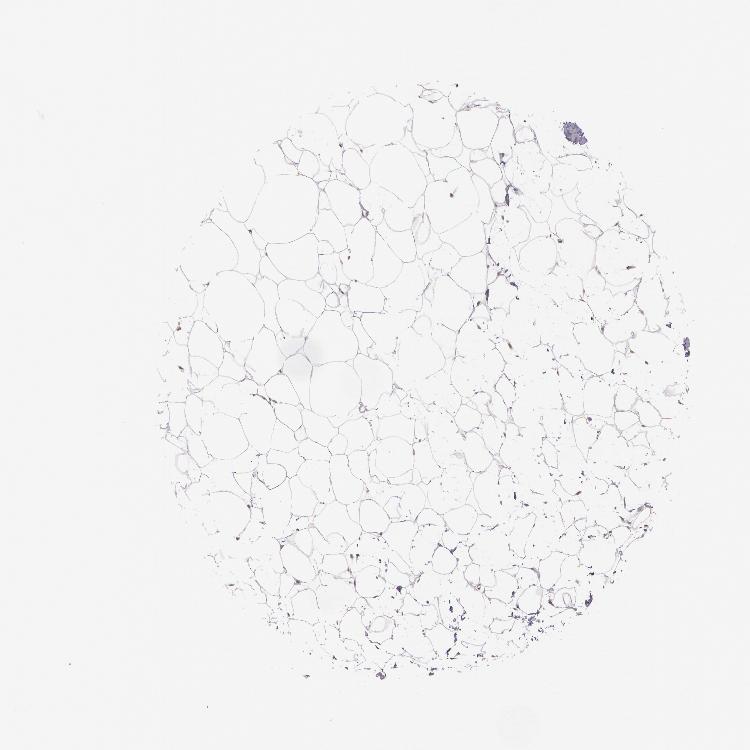

TISSUE PRIMARY DATA SOFT TISSUE Show tissue menu

SOFT TISSUE - Expression summary

SOFT TISSUE 1 - Antibody stainingi

Antibody staining in the annotated cell types in the current human tissue is reported as not detected, low, medium, or high, based on conventional immunohistochemistry profiling in selected tissues. This score is based on the combination of the staining intensity and fraction of stained cells.

Each image is clickable and will lead to virtual microscopy that enables deeper exploration of all samples and also displays staining intensity scores, fraction scores and subcellular localization as well as patient and tissue information for each sample.

Antibody HPA001499Antibody CAB004540

Chondrocytes Not detected-

Fibroblasts Not detectedNot detected